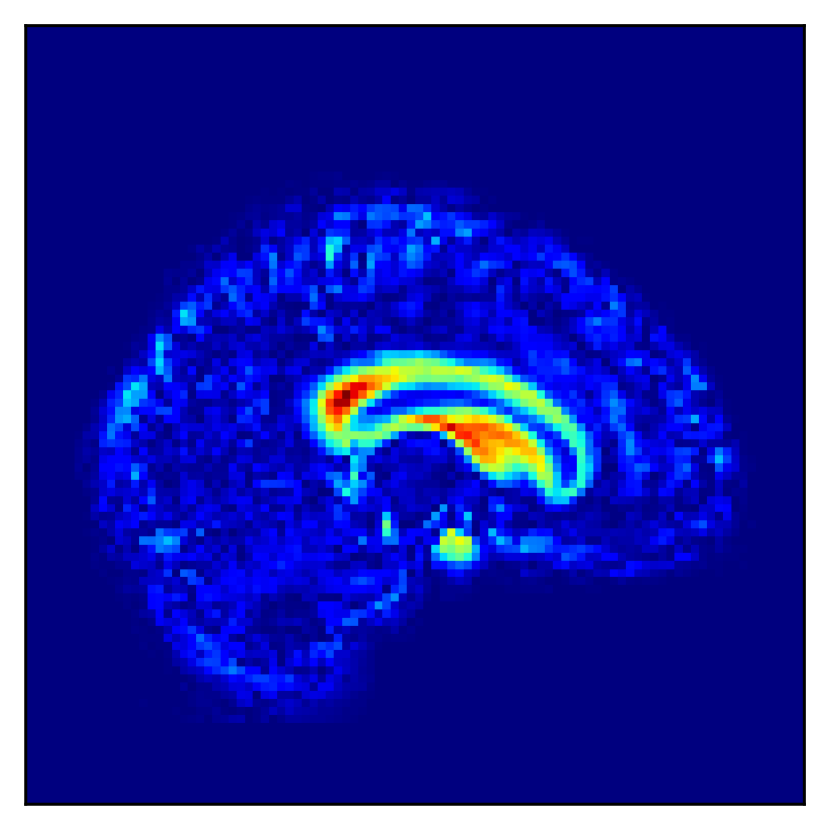

Refer to caption

(a) Coronal

(b) Sagittal

(c) Transverse

Figure 2: The difference between the mean images of the AD and CN conditions.

Fig. 2 shows one slice of the difference image between the CN and AD mean images in the ADNI database. Alzheimer’s features are located primarily near the ventricles. To assess similarity cases based on disease features, it is necessary that one dimension of the low-dimensional representation captures this region.

Fig. 5 shows the difference in the reconstructed images (the coronal, sagittal, transverse planes) with and without perturbation to one dimension of the low-dimensional representations that most affect the disease features between AD and CN. This one dimension is chosen to have the largest expected value of the difference in the mean vector (150150150 dim) between AD and CN.

In Fig. 5, the influence of dimensions that may contribute to the diagnosis of AD is examined, and it can be seen that the naïve β𝛽\beta-VAE captures not only the important areas around the ventricles shown in Fig. 2 but also the edges of the brain and other areas. Loc-VAE, however, is more limited and captures this region better. This result shows that Loc-VAE acquires a specific dimension of the disease features on low-dimensional representation. Disease feature–specific dimensions serve as materials for the neurologist to assess similar cases displayed by CBIR.